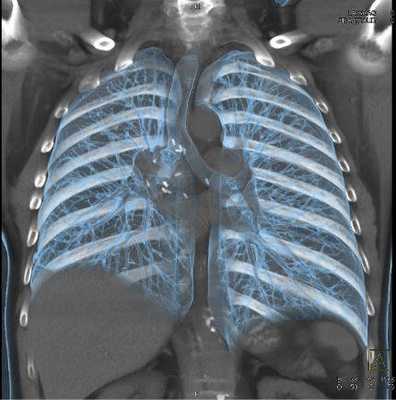

КТ органов грудной клетки - усовершенствованный способ рентгенографической визуализации, который использует излучение для создания детальных изображений грудины, грудино-ключичных суставов, ребер, прилежащих мягких тканей и органов (в первую очередь, легких).

Исследование проводят, если после выполненной обычной рентгенографии причина жалоб осталась неясной или есть подозрение на патологический процесс в данной области. Компьютерная томография органов грудной клетки может быть выполнена в качестве альтернативы МРТ, если у пациента есть противопоказания к проведению магнитно-резонансного сканирования. Для лучшей визуализации возможно введение контрастного вещества. Основным преимуществом КТ является его способность одновременно демонстрировать кости, мягкие ткани (при контрастировании) и кровеносные сосуды.Что показывает КТ грудной клетки

![Мультиспиральная КТ грудной клетки, 3D-реконструкция]()

Мультиспиральная КТ грудной клетки, 3D-реконструкция